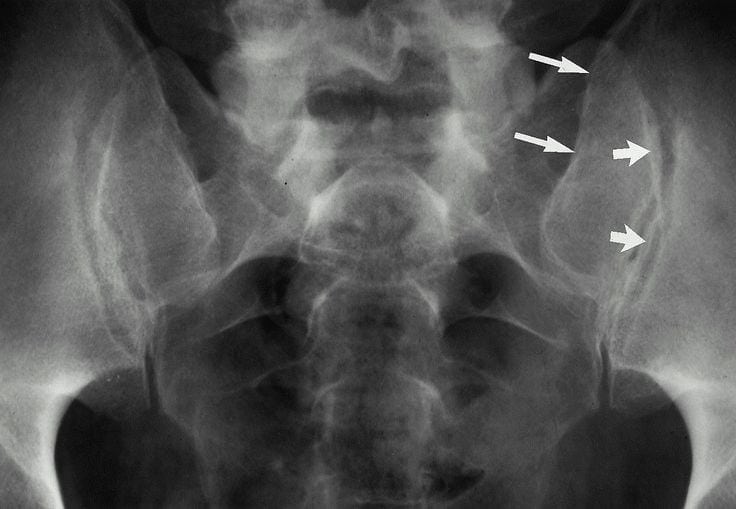

Прогрессирование патологии может приводить к развитию серьезных осложнений, например, анкилоза и контрактур. Диагноз выставляется на основании клинической картины, анамнеза, результатов рентгенографии, КТ, МРТ, артроскопии. В терапии артроза крестцово-копчикового сочленения используются консервативные методы лечения — курсовой прием препаратов, проведение физиопроцедур, занятия лечебной гимнастикой и физкультурой.

Крестцово-подвздошные сочленения

Хронический воспалительный процесс, протекающий в крестцово-подвздошных сочленениях, в большинстве случаев становится причиной их разрушения. Спровоцировать его развитие могут, как банальные травмы, так и тяжелые суставные патологии рецидивирующего характера. Обычно они относятся к системным заболеваниям, поражающим все сочленения опорно-двигательного аппарата. Частые причины артрита:

В этом участке позвоночника нередко выявляется и посттравматический артроз. Разрушение хрящевых тканей происходит в результате формирования рубцов после травмирования сочленения или проведения хирургической операции.